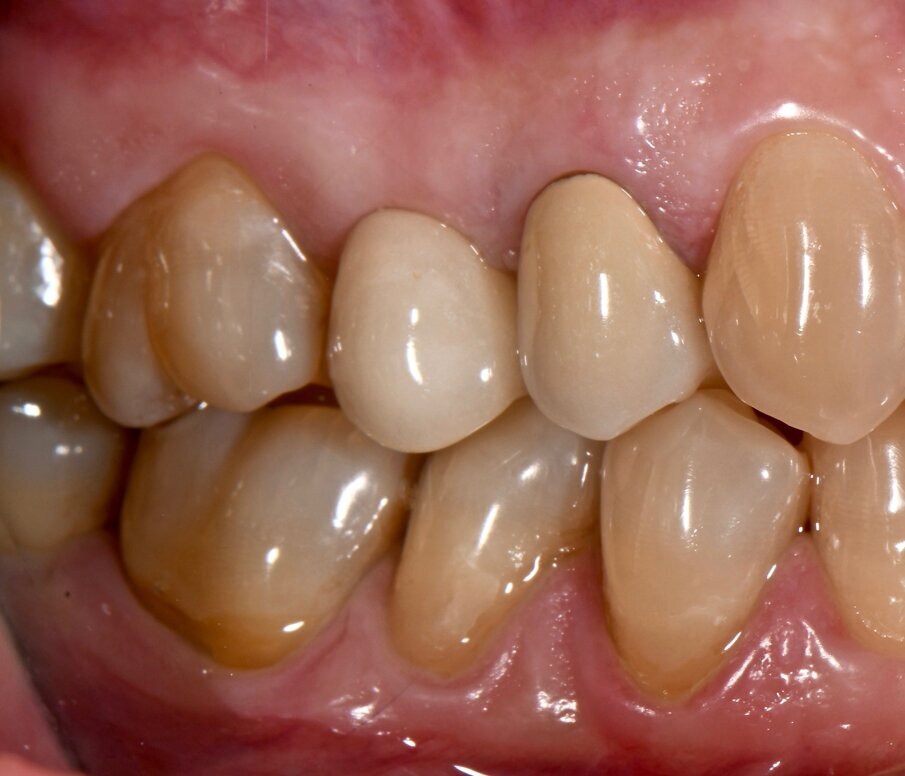

Il riscontro a 1 anno ha dimostrato una stabilità clinica per ciò che concerne il FMPS e il FMBS se comparata ai dati presi a 6 mesi. Il valore medio della profondità di sondaggio, invece, è ulteriormente migliorato di 0.34 mm e 0.67 mm rispettivamente per gli impianti 15 e 25. La rivalutazione dei parametri parodontali a 6 mesi e 1 anno è stata riportata nelle Figure 5a-6 e in Tabella 1.

Fig. 5a - Condizione clinica ad 1 anno: visione frontale.

Fig. 5b - Condizione clinica ad 1 anno: I e VI sestante.

Fig. 5c - Condizione clinica ad 1 anno: III e IV sestante.

Fig. 6 - Charting parodontale a 1 anno.

Tabella 1 - Rivalutazione parodontale a 6 mesi e 1 anno.